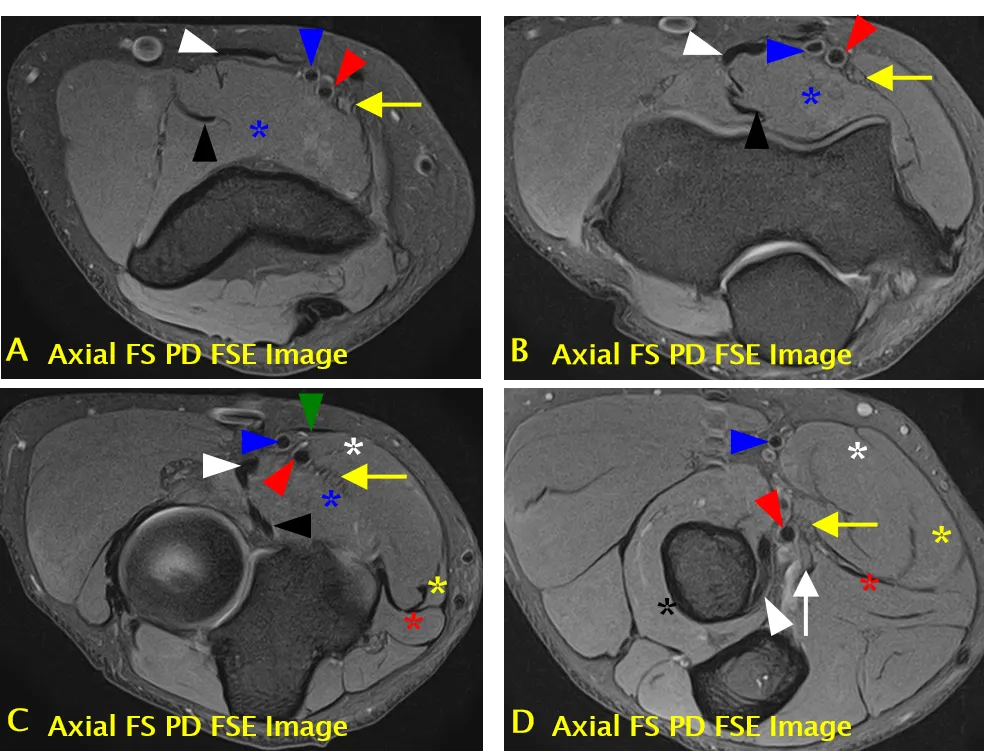

尺神经(黄色箭头标注);可见肱三头肌(长头)(A 中白色箭头标注)、指深屈肌(C 中黑色标注)、尺侧腕屈肌(肱骨头)(C 中白色标注)、尺侧腕屈肌(尺骨头)(C 中黄色标注)、尺侧腕屈肌(D 中红色标注)、指浅屈肌(C、D 中蓝色 * 标注);ME = 内上髁,OP = 鹰嘴

尺神经沟(骨纤维通道)结构

• 尺神经沟的底部由内侧副韧带后束和关节囊构成。

• 尺神经沟的顶部由尺神经沟支持带和尺侧腕屈肌筋膜深层(弓状韧带)构成。

内侧副韧带后束(蓝色箭头标注)、尺神经沟支持带(A 中箭头头标注)、弓状韧带(B 中箭头头标注)、尺神经(黄色箭头标注);可见尺侧腕屈肌(B 中黑色箭头标注)和共同屈肌肌腱(B 中白色箭头标注)。